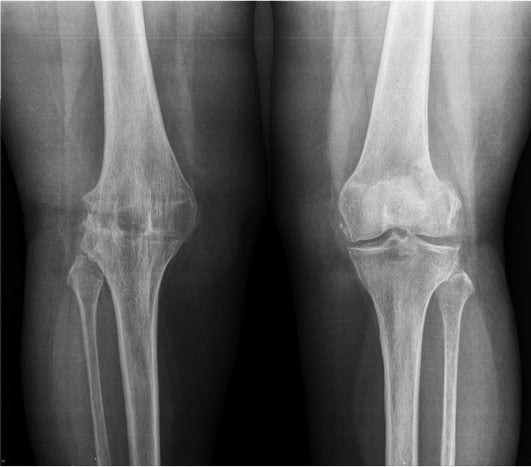

Для деформирующего артрита любой локализации характерны такие клинические и рентгенологические признаки:

- крепитация — хруст, треск, пощелкивание суставов во время их сгибания или разгибания, указывающие на истончение хрящей и ослабление связочно-сухожильного аппарата;

- ограничение подвижности сочленений из-за уменьшения размеров суставных щелей;

- разрастание остеофитов, провоцирующее развитие синовита и воспаление мягких тканей;

- необратимая деформация крупных и мелких суставов в результате дегенерации субхондральных костей;

| Стадии деформирующего артрита | Клинические и рентгенологические проявления |

| Первая | В местах крепления связок формируются своеобразные заострения. В области коленей — межмыщелковые возвышения на участке крестообразных связок, в тазобедренных сочленениях — в области надмыщелков, боковых связок большеберцовых костей. Размеры суставных щелей не изменены. Болезненные ощущения возникают только при физических нагрузках. Если лечение начинается на этом этапе, то патология надежно купируется и дальше не развивается. О заболевании будут напоминать только окостеневшие участки в местах прикрепления связок |

| Вторая | Суставные щели сужены в результате изнашивания гиалиновых хрящей. Замыкательная пластинка склерозируется, уплотняется. Стадии ремиссии чередуются с рецидивами, возникающими все чаще. Объем движений в суставах существенно снижается, при сгибании или разгибании сустава слышится щелчки, хруст. Болезненные ощущения появляются даже в состоянии покоя, провоцируя бессонницу, быструю утомляемость. При диагностировании патологии используются консервативные методы лечения, редко дающий положительный результат |

| Третья | На рентгенологических изображениях заметно полное или частичное сращение суставных щелей и множество сформировавшихся крупных остеофитов около сочленений. Артралгия становится постоянной, усиливается при малейшем движении. Суставы тугоподвижны в течение всего дня из-за развившегося анкилоза. Консервативное лечение не эффективно, направлено только на устранение болей. Пациента готовят к хирургическому вмешательству — корригирующей остеотомии, но чаще к эндопротезированию |

Лечением деформирующего артрита занимаются ревматологи или ортопеды, постравматического — травматологи. Если в штате больницы таких специалистов нет, нужно записаться на прием к терапевту. Первичный диагноз выставляется на основании жалоб пациента, его внешнего осмотра, изучения анамнеза. Для подтверждения проводится ряд инструментальных и лабораторных исследований. Наиболее информативна рентгенография, позволяющая выявить все характерные признаки деформации суставов — субхондральный остеосклероз, сузившуюся щель, сформировавшиеся кисты и остеофиты.